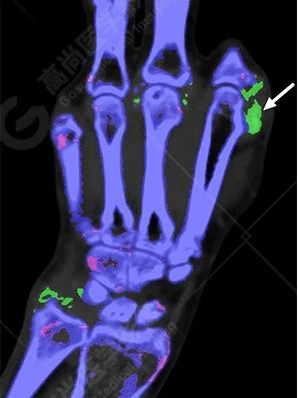

雙能CT痛風(fēng)染色圖像:

白色箭頭提示痛風(fēng)石沉積。